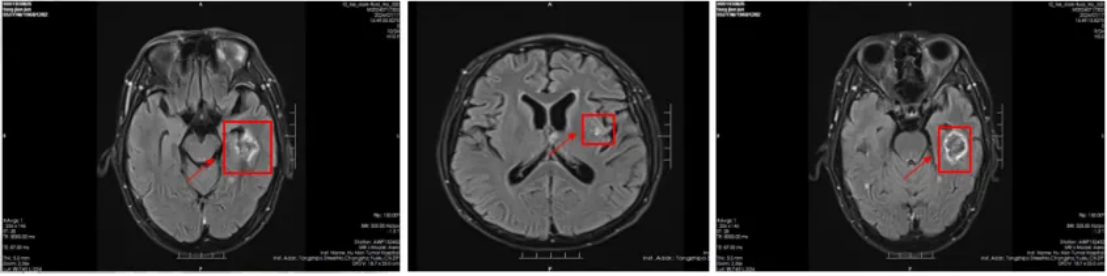

治疗前头部(2024-5-14):脑内多发结节肿块,考虑转移瘤可能性大(图3)。

图3

治疗后头部(2024-7-17):脑内多发转移瘤较前明显缩小,减少,活性降低(图4)。

图4